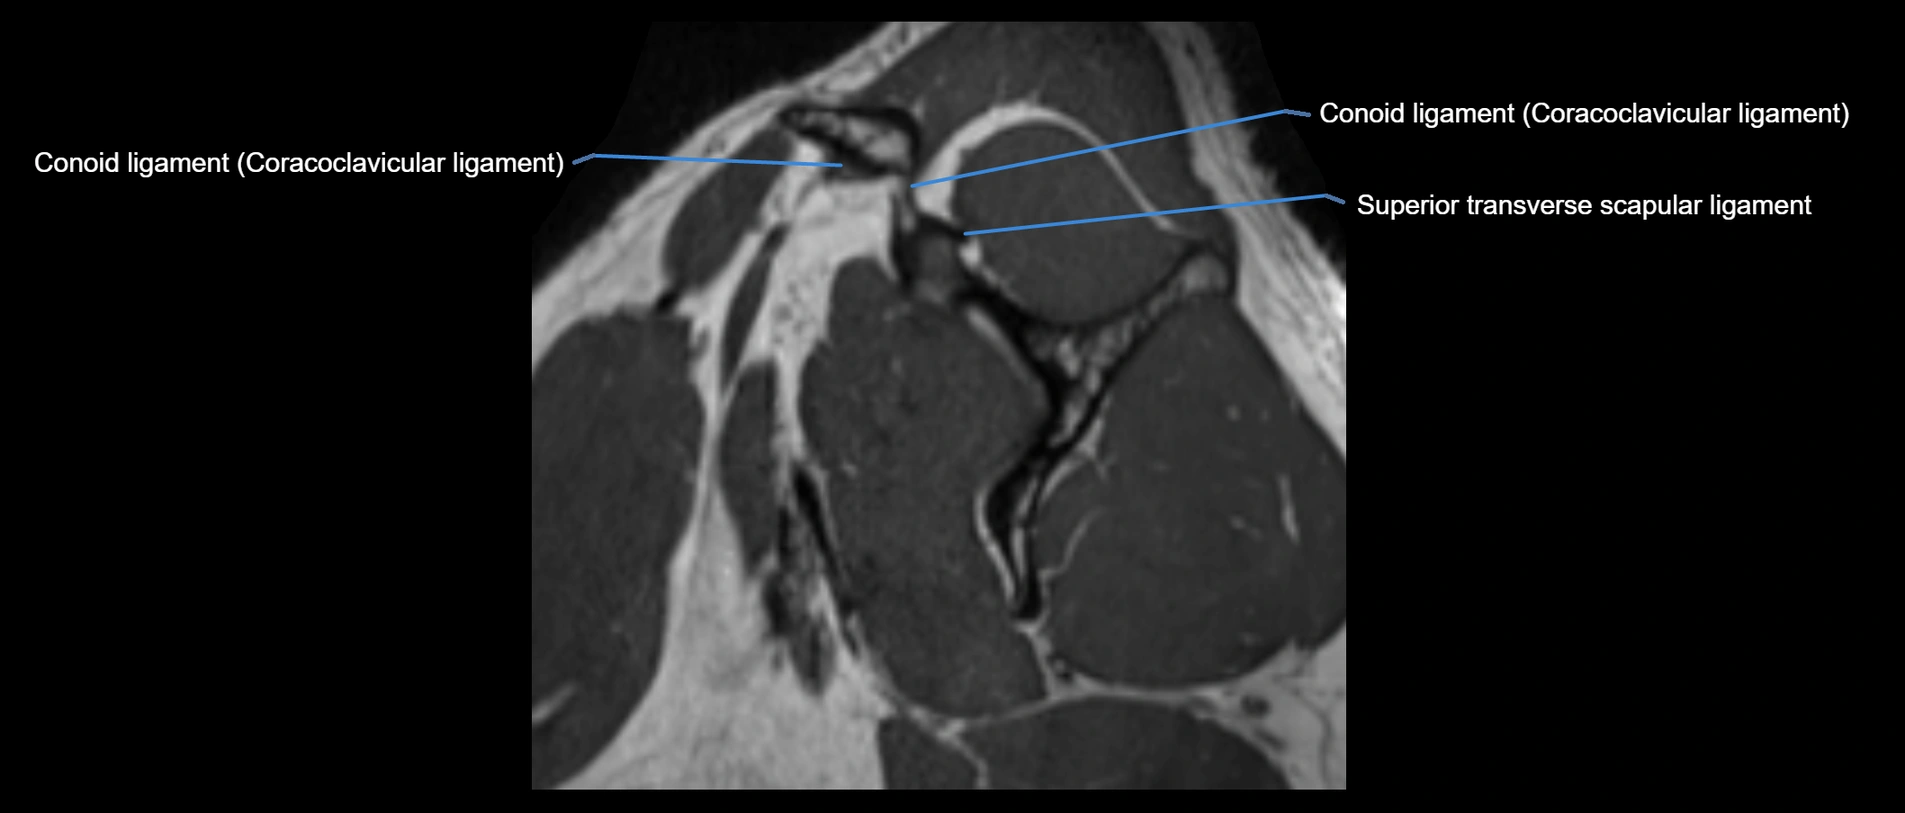

MRI Appearance

• T1-weighted images:

• Normal ligament: Low signal (dark linear band) spanning acromion to clavicle.

• Surrounding fat planes: Bright, delineating the ligament clearly.

• Marrow of clavicle and acromion: Bright due to fatty content.

• Tears: Discontinuity or irregular thickening with intermediate-to-bright signal.

• Chronic injury: Thinning, fraying, or irregular low-signal fibers with adjacent scarring.

• T2-weighted images:

• Normal ligament: Low signal, homogeneous.

• Partial tear or sprain: Focal hyperintensity or thickening.

• Complete tear: Discontinuity with fluid-bright gap between clavicle and acromion.

• Associated edema: Bright signal in distal clavicle or acromion marrow.

MRI images

image